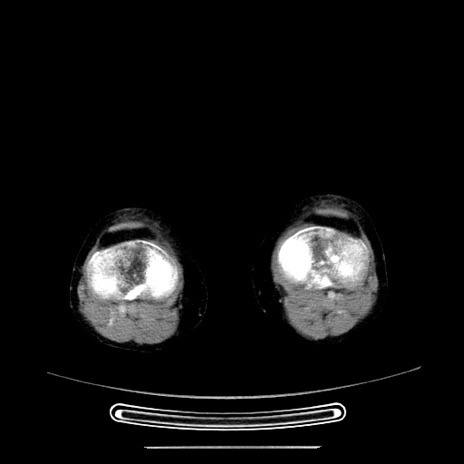

症例5(横断像)

【症例】70歳代女性

【主訴】お腹が張る

【現病歴】1週間くらい前から腹部膨満の自覚あり。昨日夜から増悪したため、本日救急外来受診。

【身体所見】意識清明、BT 36.5℃、BP 165/106mmHg、HR 80bpm、SpO2 98%、腹部:膨満、軟、自発痛・圧痛なし、触診にて不快感あり、腸蠕動音:減弱

【データ】WBC 12600、CRP 1.04